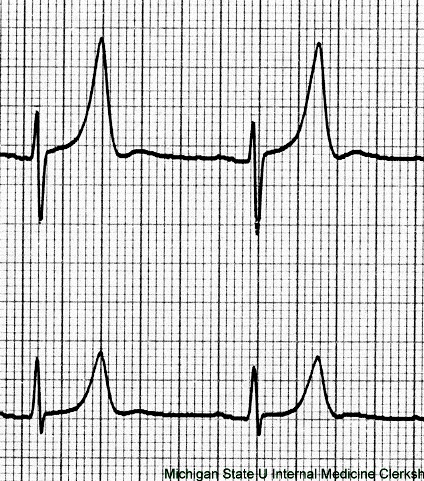

TaSTy scoop: chronic digoxin use may cause "scooped" concave ST segments on ECG

Wide QRS shaped crack: class I antiarrhythmics widen the QRS complex on the ECG (decreased AP conduction velocity) (faster cells bind more and slow down more) (QRS widen as HR increases)

Twisted torsades streamer: class IA antiarrhythmics can cause Q-T interval prolongation (precipitates torsades) (K channel prolongation)

Public Relations: heart block manifests as a prolonged PR interval on ECG

Public Relations: non-dihydropyridine CCBs prolong the PR interval on ECG

Peaked streamer: hyperkalemia can cause peaked T waves (with shortened QT interval) on ECG

Streamer with extra bump: hypokalemia can induce U waves at the end of the T wave on ECG